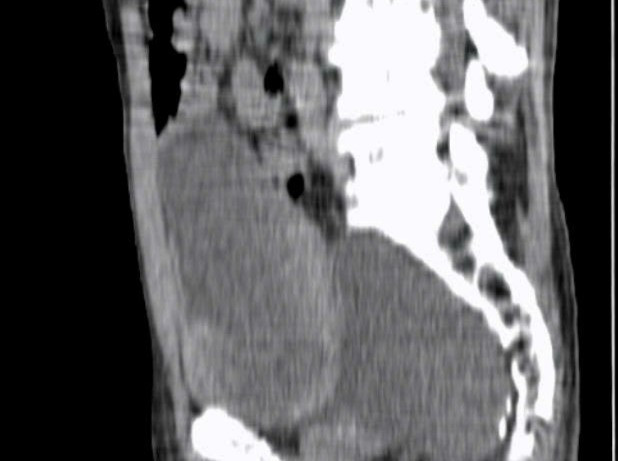

Kết quả CT-Scanner cho thấy người bệnh bị phì đại tuyến tiền liệt gây tắc nghẽn đường tiểu dưới, đồng thời có túi thừa bàng quang kích thước lớn. Túi thừa này hoạt động như một "bàng quang thứ hai", khiến dòng tiểu ứ đọng, gây tiểu khó, tiểu không hết và tăng nguy cơ viêm nhiễm đường tiết niệu. Nếu kéo dài, tình trạng này có thể ảnh hưởng đến chức năng thận.

Hình ảnh bệnh nhân có "hai bàng quang"/Ảnh BV

Người bệnh bị phì đại tuyến tiền liệt gây tắc nghẽn đường tiểu dưới, đồng thời có túi thừa bàng quang kích thước lớn. Ảnh BV